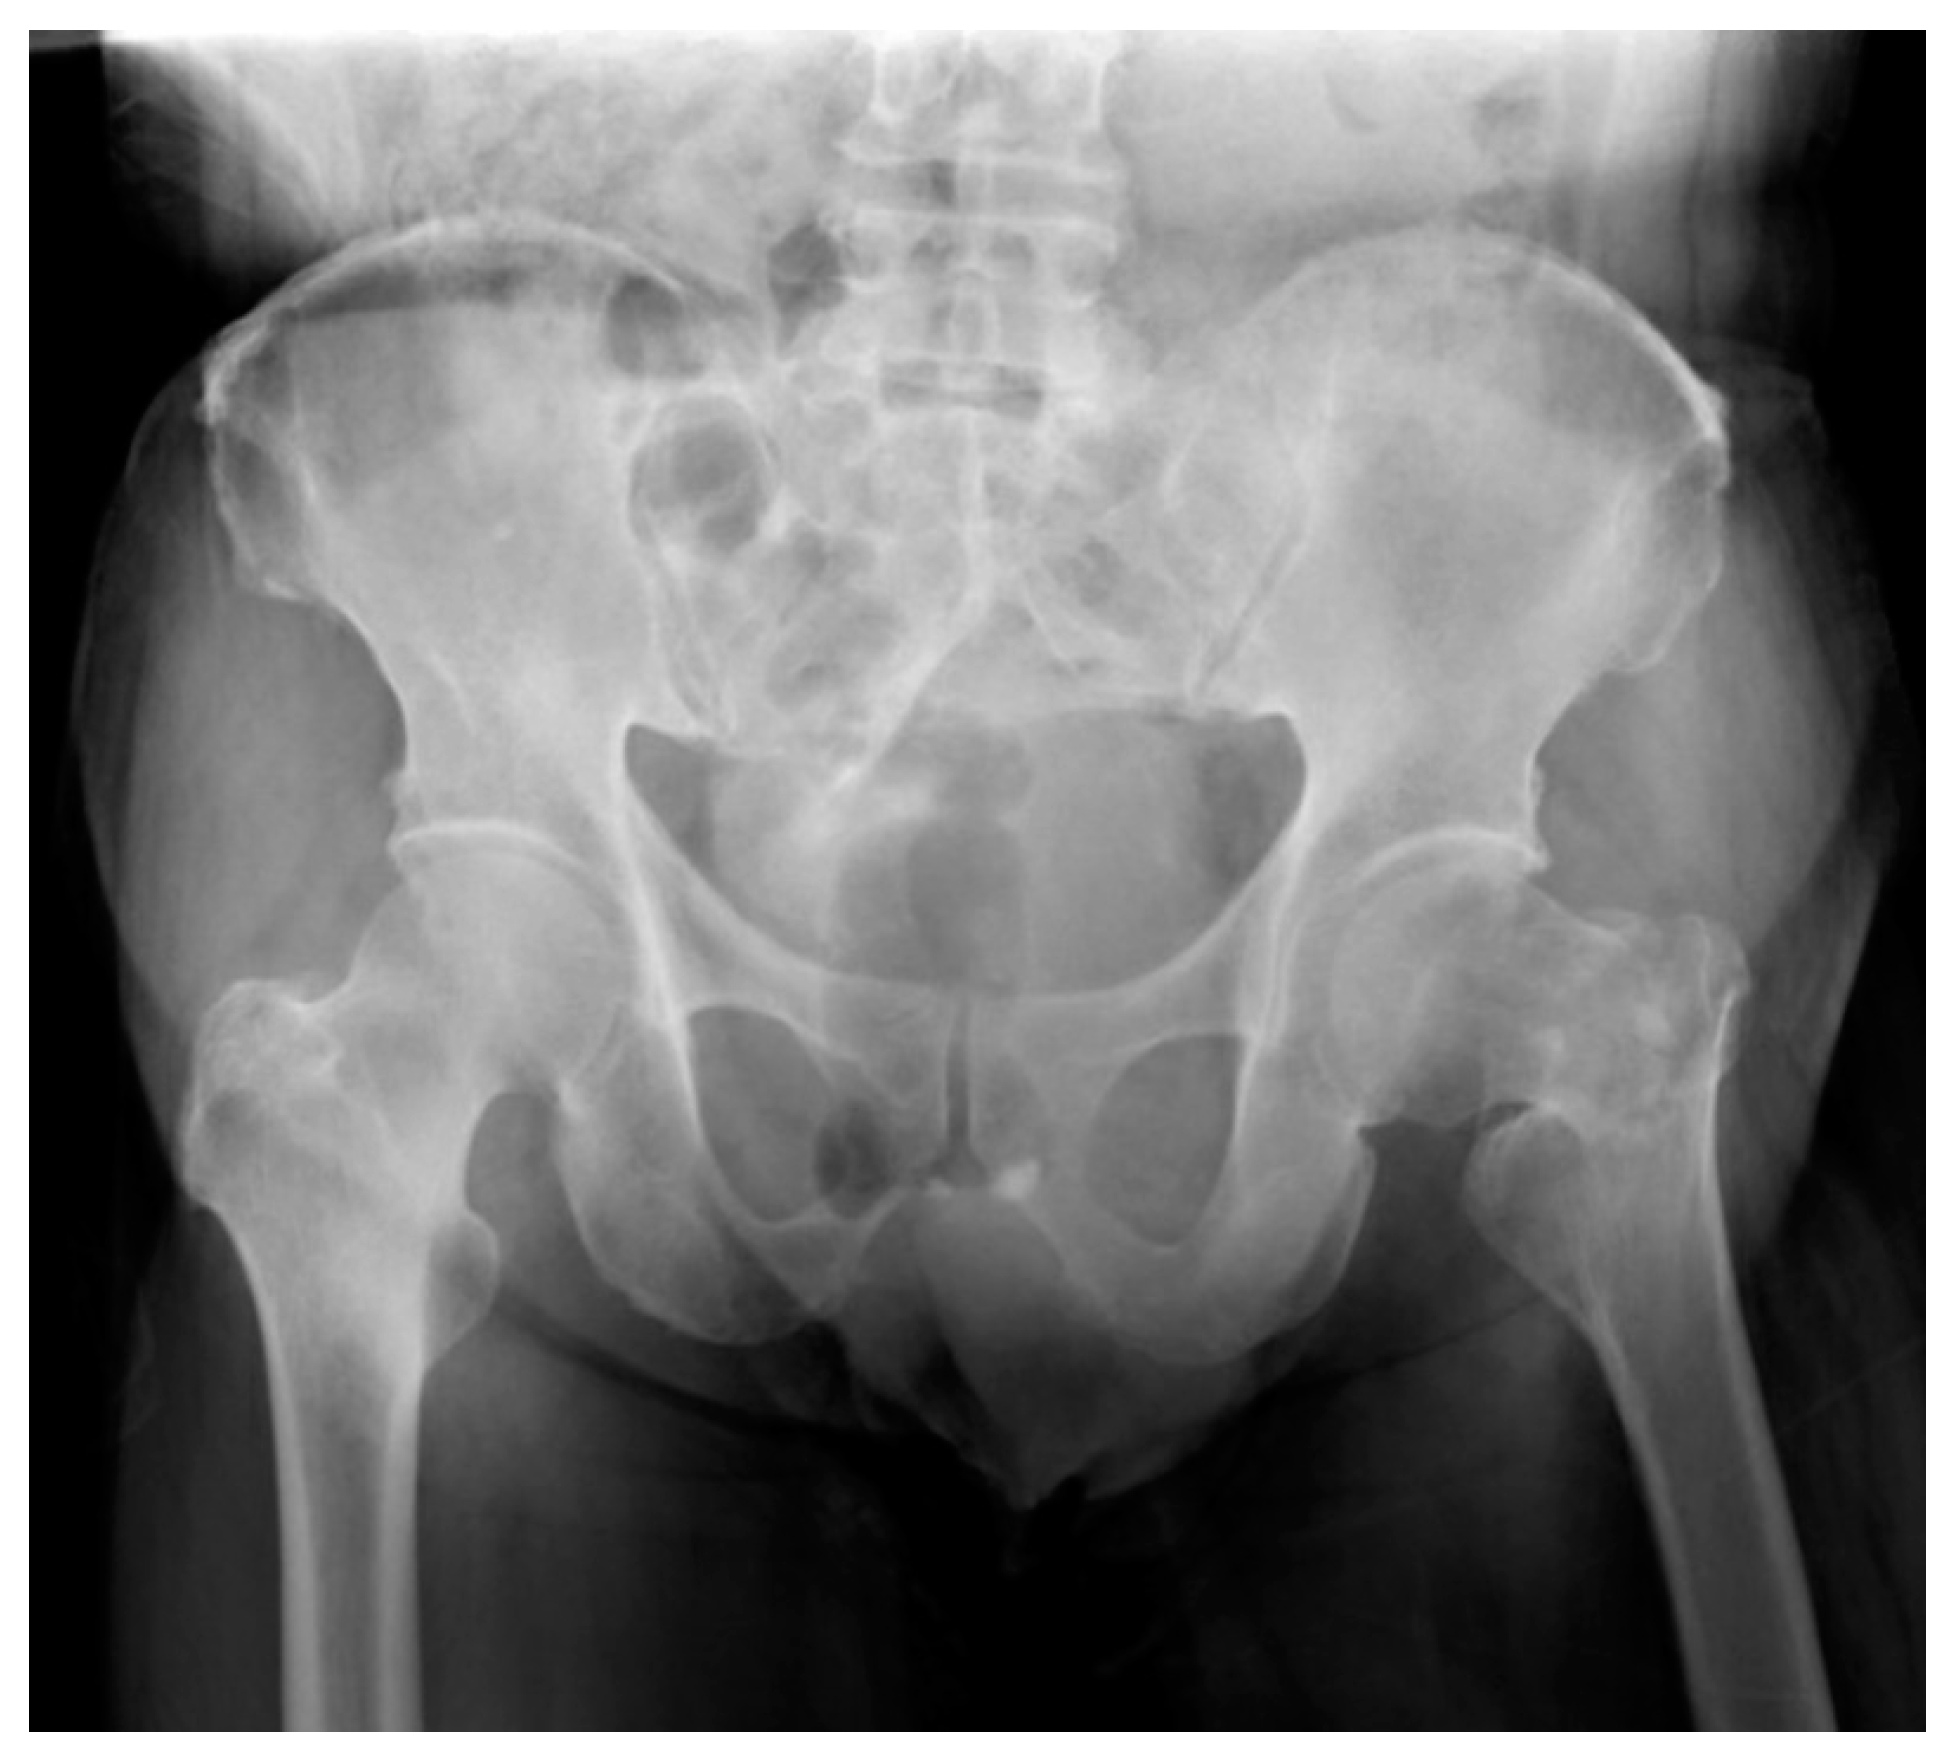

2. Case Report